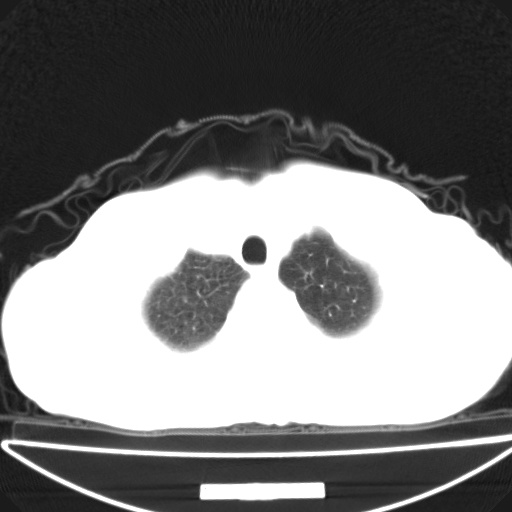

以下是引用jsgdoctor在2008-11-6 22:12:00的发言:[br]右主支气管壁明显增厚,管腔狭窄.考虑为右侧中央型肺癌伴阻塞性炎症\\肺脓肿.

以下是引用zjzjr在2008-11-6 20:25:00的发言:[br]中心型肺ca,合并阻塞性肺炎

以下是引用zsl6918在2008-11-6 19:43:00的发言:[br]右侧中心性肺癌(鳞癌)